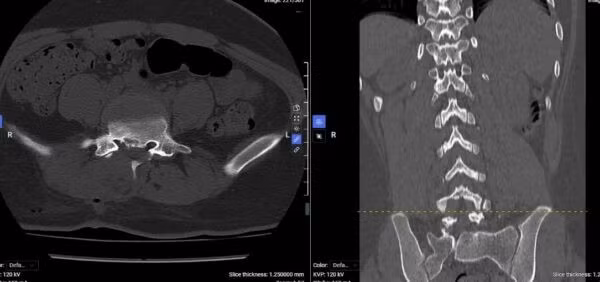

Phim chụp thể hiện vị trí thoát vị của người bệnh B.G.H khi vào viện - Ảnh BVCC

Tại bệnh viện, qua thăm khám lâm sàng kết hợp với các xét nghiệm và chẩn đoán hình ảnh, bác sĩ xác định người bệnh mắc thoát vị đĩa đệm đốt sống thắt lưng L4–L5 lệch phải, gây chèn ép rễ thần kinh.